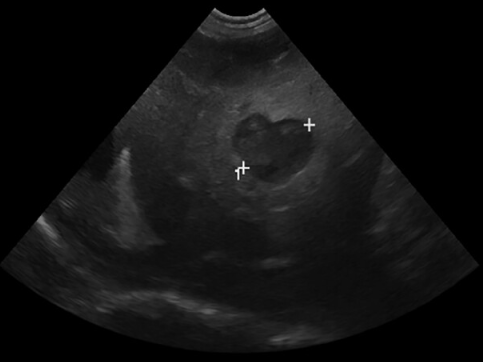

초음파 소견에서 주의 깊게 생각해 볼 문제가 있다.

이런류의 비특이적인 cyst가 무증상 환자에서도 종종 관찰되곤 하는데 이들에 대한 검사가 필요할 수 있다는 사실을 염두에 둬야 한다. 또한 증상이 없더라도 모니터링을 통해 변화 양상을 확인할 근거가 된다.